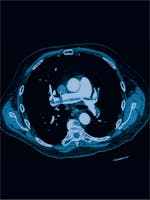

Trombembolism pulmonar - Cauze, simptome, tratament

Această afecțiune provoacă dureri severe, dispnee și o senzație de anxietate marcată, iar pacientul trebuie să se prezinte de urgență la medicul specialist, pentru o intervenție terapeutică.